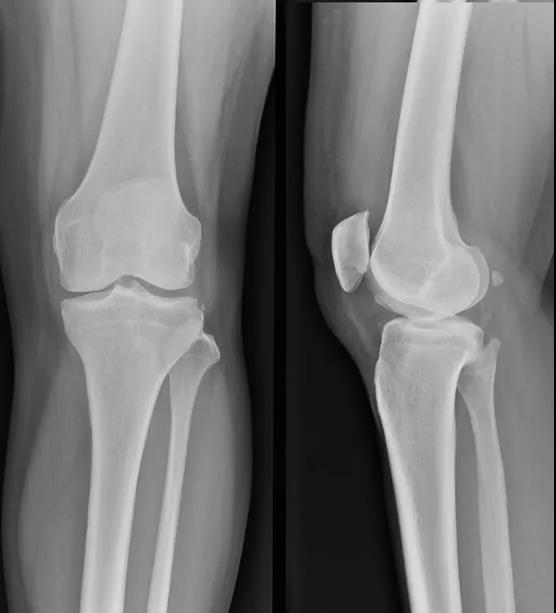

膝关节穿刺术常用于检查关节腔内积液的性质,或抽液后向关节腔内注药。膝关节腔内积液,需行关节穿刺抽液检查或引流,或注射药物进行治疗。关节腔内注射空气或造影剂,行关节造影术,以了解关节软骨或骨端的变化。

1、以髌骨中心点,作水平线和垂直线,其第一和第二象限,各做45度的平分角,该平分线与髌骨内外缘的交点,即是进针点。

2、患者仰卧位,膝关节伸直,髌骨上缘与髌骨内外侧缘的交点为两点,斜向髌股关节中心,以45°角穿刺。

3、膝关节微屈30°左右,从髌骨下方的髌韧带内侧或外侧关节间隙垂直进针。

髌骨外上缘穿刺法

定位:髌骨外上缘处与股外侧肌交界处。按压股外侧肌下凹陷处,贴指甲刺入0.5-1cm,有落空感即可。

髌骨外下缘(外侧膝眼)穿刺法

定位:屈膝90°位,髌骨下缘、髌韧带外侧1cm处(外侧膝眼,可看到一小凹陷)。

方法:用指甲定位好后,消毒患处,针头与胫骨平台平行,向内呈45度角,穿刺进入,针头完全刺入即可。

如何选择?髌骨外下缘or髌骨外上缘

(1)对于关节内有大量积液的病人,采用髌骨外上缘进针抽液,然后顺便注射玻璃酸钠。因为关节内有大量积液的时候,积液大多在髌上囊,髌股关节间隙也比较大,髌骨外上缘进针很容易操作,也可抽出积液。而对于没有关节积液的病人,髌骨外上缘进针不太容易操作。

(2)对于没有关节积液的病人,采用髌骨外下缘(外侧膝眼)穿刺法,一定要定好位置(屈膝90度位,髌骨下缘、髌韧带外侧1cm处),采用8号针头,与胫骨平台平行,向内呈45度角,针头完全刺入,有一种落空感,有时回抽会抽出关节液,此时可放心注射;回抽如没抽出关节液,可以注射玻璃酸钠,如果注射时比较轻松,那就没有问题,如果注射时比较费力,病人感觉痛、胀,可以进一步向里面插下针头,左右移动下,注射时比较轻松,病人无不适即可再注射。只要熟练操作,定位正确,及时调整,病人很少出现注射后不适的。